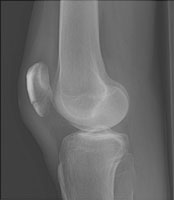

Patellar Fracture

Patellar fractures are classified according to Holt and Larson. The transverse fractures is the most common, resulting from a direct blow. Others include vertical, comminuted, and avulsed. Differentiation is made from a bipartite patella, located usually at the superolateral margin.

- Click on the image for a larger versionAAP radiograph of the knee. No definite fracture is seen.

- Click on the image for a larger versionBLateral radiograph of the knee. This depicts the fracture through the inferior pole of the patella.